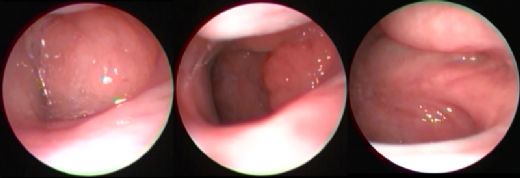

Kronik bademcik iltihabı yaşadığınız belirtilerden anlaşılıyor. Bu durumda tedavi için birkaç adım atabilirsiniz. Öncelikle bir kulak burun boğaz (KBB) uzmanına başvurarak detaylı bir muayene olmalısınız. Doktorunuz, bademciklerinizi inceleyerek gerekirse kan testleri ve boğaz kültürü gibi ek tetkikler yapabilir.

Eğer durumunuz ciddi ise ve sık sık enfeksiyon yaşıyorsanız, doktorunuz bademcik ameliyatı (tonsillektomi) önerebilir. Bu, bademciklerin tamamen alınmasını içerir ve kronik enfeksiyonların önüne geçebilir. Alternatif olarak, antibiyotik tedavisi veya diğer ilaçlarla enfeksiyonlar kontrol altında tutulabilir.